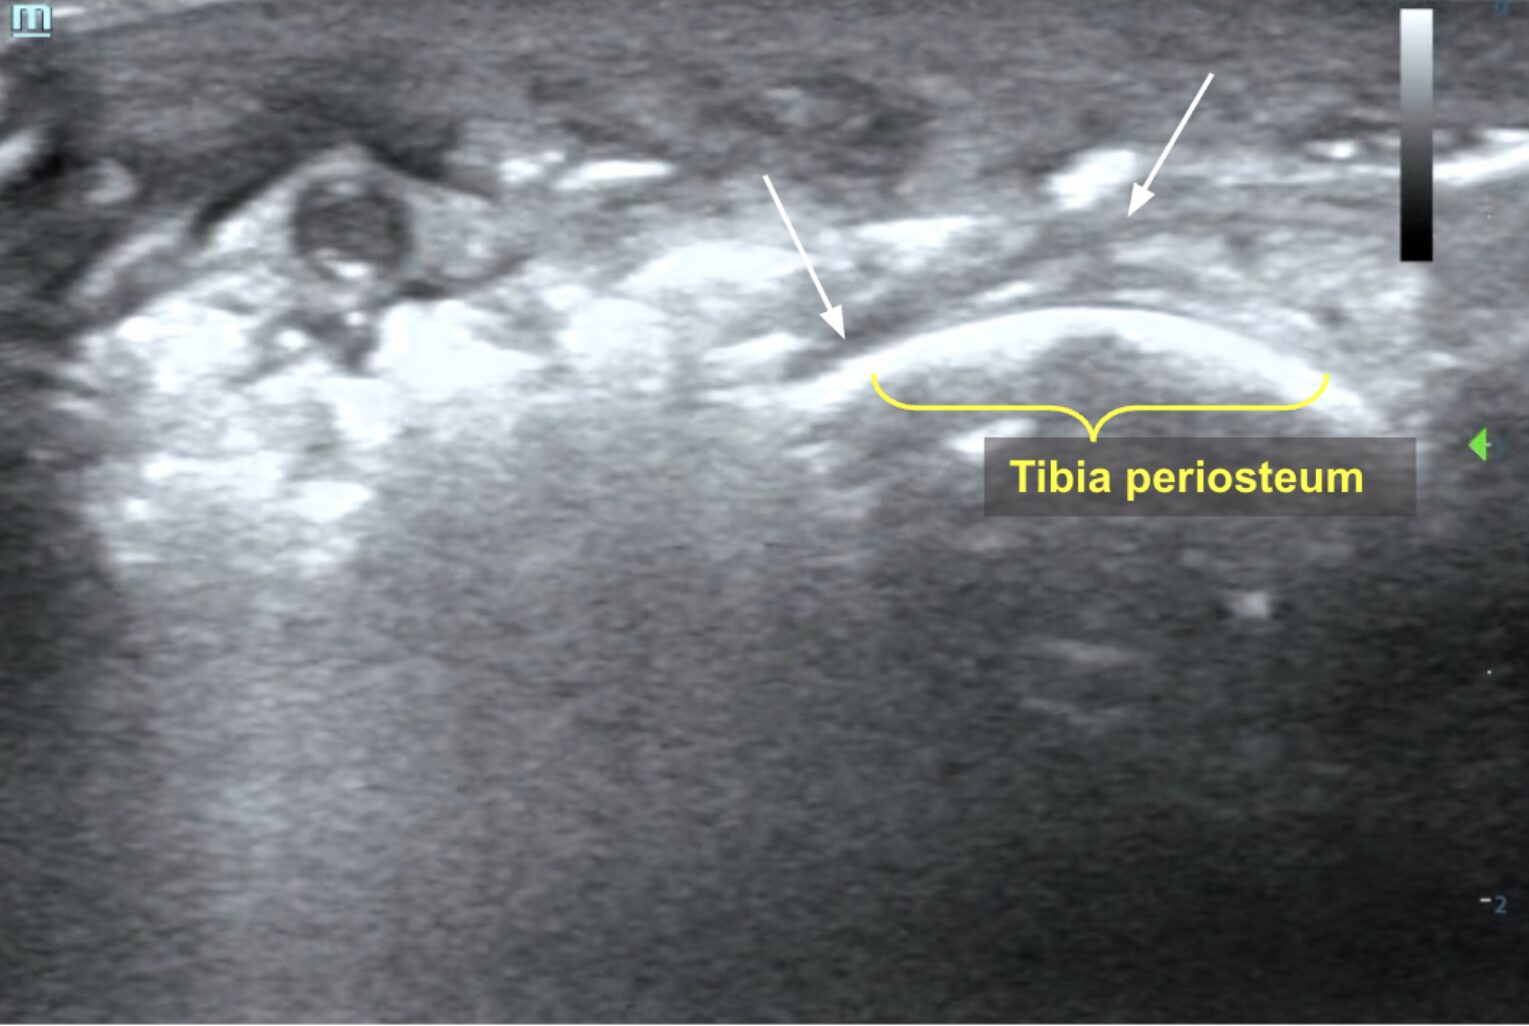

Presence of fascial fluid appears as hypoechoic to anechoic layering deep to subcutaneous tissues along the fascial plane superior to and in between muscle layers (Image 3, Video 2).

Image 3: Fascial fluid in the form of anechoic linear streaking (white arrows) visualized deep to the subcutaneous tissue invading deep to the muscle and overlying the tibia in cross-section. Images courtesy of Dr. Shepherd and Dr. Alerhand

Video 2: Linear transducer view of the tibia in short-axis showing anechoic layering along fascial planes just superior to bone (hyperechoic line in far field). Images courtesy of Dr. Shepherd and Dr. Alerhand